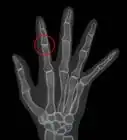

- If you will be undergoing any surgeries under anesthesia and you have RA, your doctor will likely order a neck X-ray to rule out neck and spine changes due to RA. Cervical C1-C2 subluxation is a risk when your neck is propped up during surgery, so your surgeon will need to be aware of any neck problems so they can take precautions.[16]Thanks!